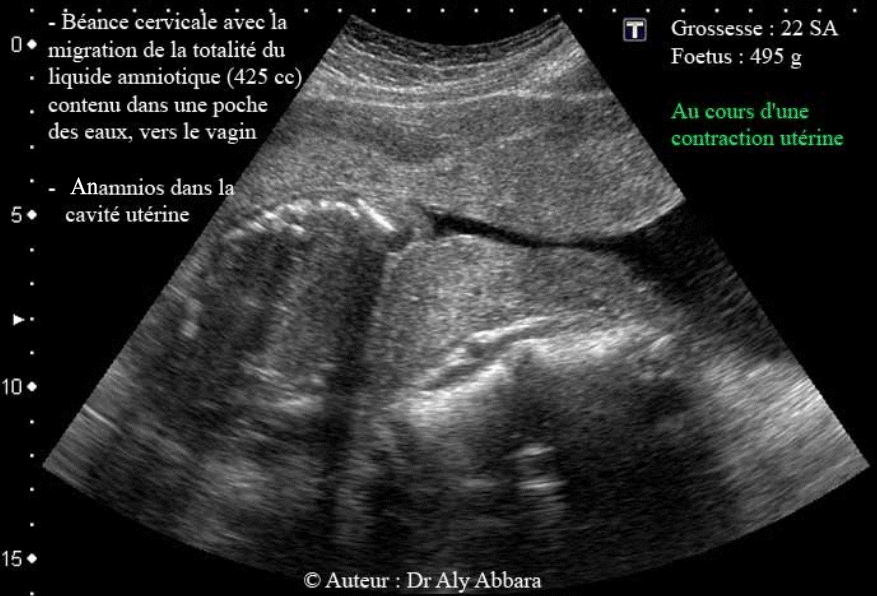

Béance du col utérin à 22 SA - Poche des eaux dans le vagin

Images échographiques montrant la conséquence d'une béance congénitale de l'orifice interne du col utérin : le fœtus est retenu dans la cavité utérine marquée par la présence d'un anamnios suite à la migration de la totalité du liquide amniotique (soit 425 cc contenu dans une poche des eaux) vers le vagin. On peut aussi observer à travers ces images la béance de la totalité du canal cervical lors des contractions utérines.

La rétention du fœtus (âgé de

22 SA - est pesant 495 g) dans la cavité utérine a été favorisée par sa présentation vicieuse, "transverse" qui empêchait son engagement et son expulsion, d'où la migration, vers le vagin, de la poche des eaux et la totalité du volume du liquide amniotique (425 cc) à travers le canal cervical béant.